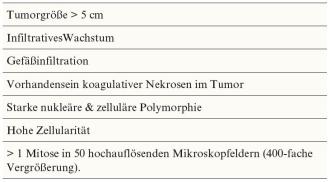

Grundsätzlich sind PECome von unsicherem malignen Potential, die Prognoseeinschätzung ist aufgrund der Seltenheit dieser Tumoren jedoch schwierig. Entsprechend der Literatur kann mit einer Gesamtüberlebensrate von 92 % gerechnet werden, wobei knapp ein Fünftel der Patientinnen am Ende einer Beobachtungszeit von median 30 Monaten Metastasen oder ein Lokalrezidiv aufweisen [Folpe AL et al.; Am J Surg Pathol (2005); 29: 1558–1575]. Bei unserer Patientin waren mehrere prognostische Marker erfüllt, die für ein höheres Risiko für ein aggressives Verhalten gesprochen haben: Grösse >5 cm, Mitoserate >1/50 HPF sowie Nekrose. Die morphologischen Hinweiszeichen auf einen malignen Verlauf sind in Tabelle 1 zusammengefasst.